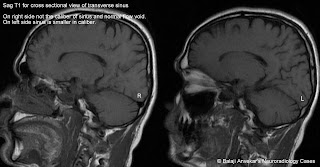

sinus transverse hypoplastic abnormal signal mri normal sag t2 t1 flair sigmoid hypoplasia flow void frcr anvekar balaji dr signals